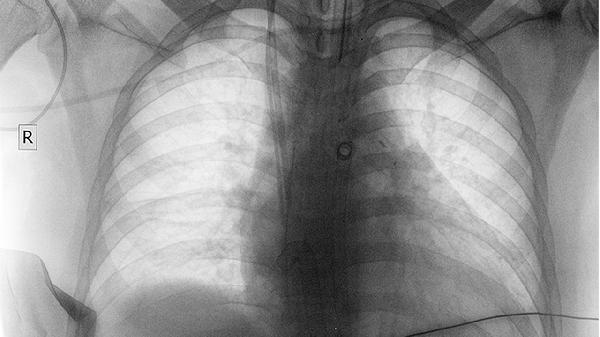

肺部肿瘤占位影响气体交换时,动脉血氧分压下降可致脑缺氧性头晕。患者多伴有呼吸困难、口唇发绀。可通过吸氧改善症状,同时使用注射用培美曲塞二钠、卡铂注射液等化疗药物控制肿瘤进展。

肺癌患者出现头晕时应卧床休息避免跌倒,保持环境通风。饮食需增加瘦肉、动物肝脏等富含铁的食物,限制每日饮水量以防加重低钠血症。定期监测血常规、血气分析及电解质指标,若头晕持续或加重需立即复查胸部CT排除脑转移。治疗期间避免突然改变体位,起身时动作宜缓慢。